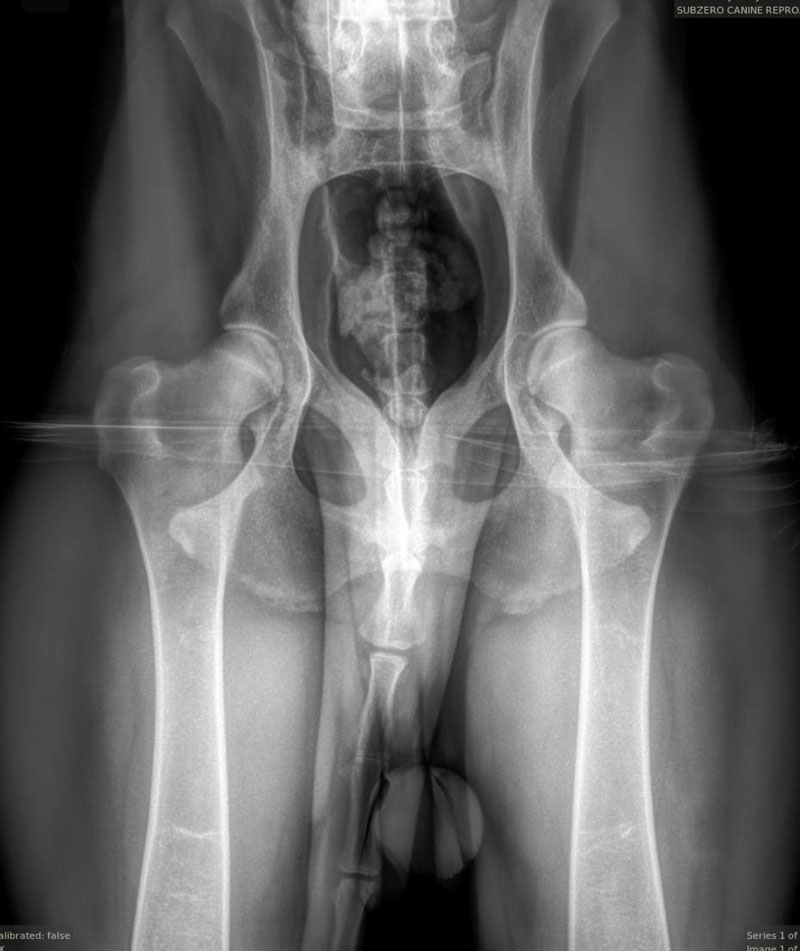

We are proud to offer state of the art Idexx radiology technology and equipment, which allows the clearest of images to be provided to our clientele. This is especially helpful when needing to determine final puppy count prior to whelp. The best time to perform a pregnancy radiograph is 55 days or later from breeding. An appointment is required for this service.

We are also proud to offer OFA (Orthopedic Foundation for Animals) image submissions. This is a requirement amongst many AKC breed clubs and may include several different image types such as:

We frequently receive inquiries regarding our success with proper positioning for OFA images, specifically for hips. Translating this success can be challenging, so we have included images of various breeds that we have taken. We take great pride in our success with these images and many others like them. As extreme perfectionists, we appreciate owners who understand that we strive for the best technique and outcome while minimizing stress and ensuring the comfort of your dog(s), particularly since all images taken here are done WITHOUT sedation.